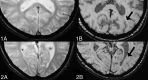

Background and purpose: Cerebral microbleeds are thought to have potentially important clinical implications in dementia and stroke. However, the use of both T2* and SWI MR imaging sequences for microbleed detection has complicated the cross-comparison of study results. We aimed to determine the impact of microbleed sequences on microbleed detection and associated clinical parameters.

Materials and methods: Patients from our memory clinic (n = 246; 53% female; mean age, 62) prospectively underwent 3T MR imaging, with conventional thick-section T2*, thick-section SWI, and conventional thin-section SWI. Microbleeds were assessed separately on thick-section SWI, thin-section SWI, and T2* by 3 raters, with varying neuroradiologic experience. Clinical and radiologic parameters from the dementia investigation were analyzed in association with the number of microbleeds in negative binomial regression analyses.

Results: Prevalence and number of microbleeds were higher on thick-/thin-section SWI (20/21%) compared with T2*(17%). There was no difference in microbleed prevalence/number between thick- and thin-section SWI. Interrater agreement was excellent for all raters and sequences. Univariate comparisons of clinical parameters between patients with and without microbleeds yielded no difference across sequences. In the regression analysis, only minor differences in clinical associations with the number of microbleeds were noted across sequences.